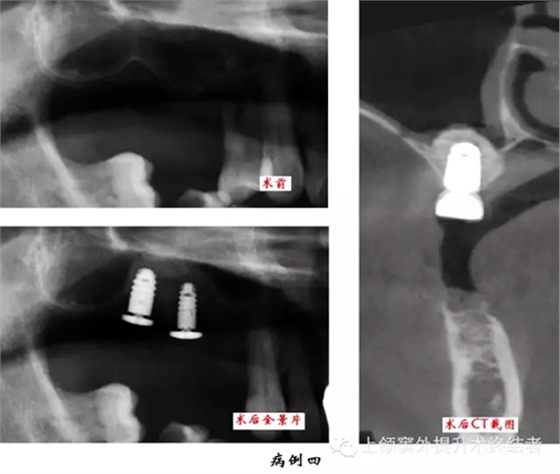

術(shù)前檢查口腔內(nèi)情況,主要包括骨和粘膜的狀況。拍攝曲體層片,測量并按其放大率計數(shù)上頜竇底至牙槽嵴頂?shù)木嚯x,檢查上頜竇形態(tài)和密度,排除無癥狀的上頜竇慢性炎癥或囊腫等。觀察竇內(nèi)有無上頜竇橫隔,位置是否影響手術(shù)操作,如有影響則需調(diào)整開窗位置。拍攝直線體層片和上頜竇矢狀面體層片可以顯示上頜竇底斷面或矢狀面的現(xiàn)狀,但以上圖像都有一定程度的放大失真。如有條件采用三維螺旋CT進行掃描可以準(zhǔn)確測量上頜竇底至牙槽嵴頂?shù)膶嶋H距離,觀察上頜骨形態(tài),分析術(shù)區(qū)條件和檢查上頜竇健康狀況,以利于進行術(shù)前診斷和制定治療計劃。上頜竇底提升同期種植術(shù)前應(yīng)制作手術(shù)模板。